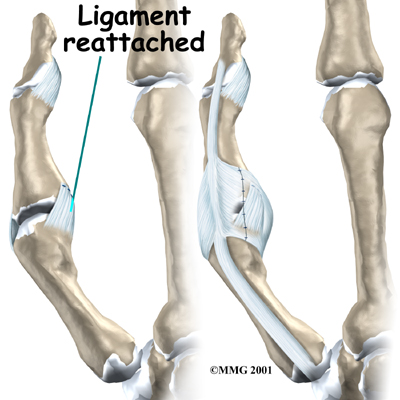

If the ligaments are completely torn, you will most likely have surgery to repair them. A torn ligament cannot fully heal itself. Surgery for the thumb collateral ligaments is usually done as an outpatient procedure, meaning you will probably go home the same day as the surgery.

Suture Repair

In the surgery, your surgeon will make a small V- or S-shaped cut over the back of the MCP joint of the thumb.

This helps isolate and protect the nerve branches running up your thumb. Your surgeon will then cut through a sheet of tissue called the adductor aponeurosis.

This helps expose the MCP joint and the ligaments. The area around the injury is examined for any soft tissue damage. Your surgeon then repairs the ligaments with stitches that anchor them back to the bone.

Patients usually have good results when suture repair is done within four weeks after the injury. After surgery, pain and stiffness are usually minimal, and thumb strength will normally return.